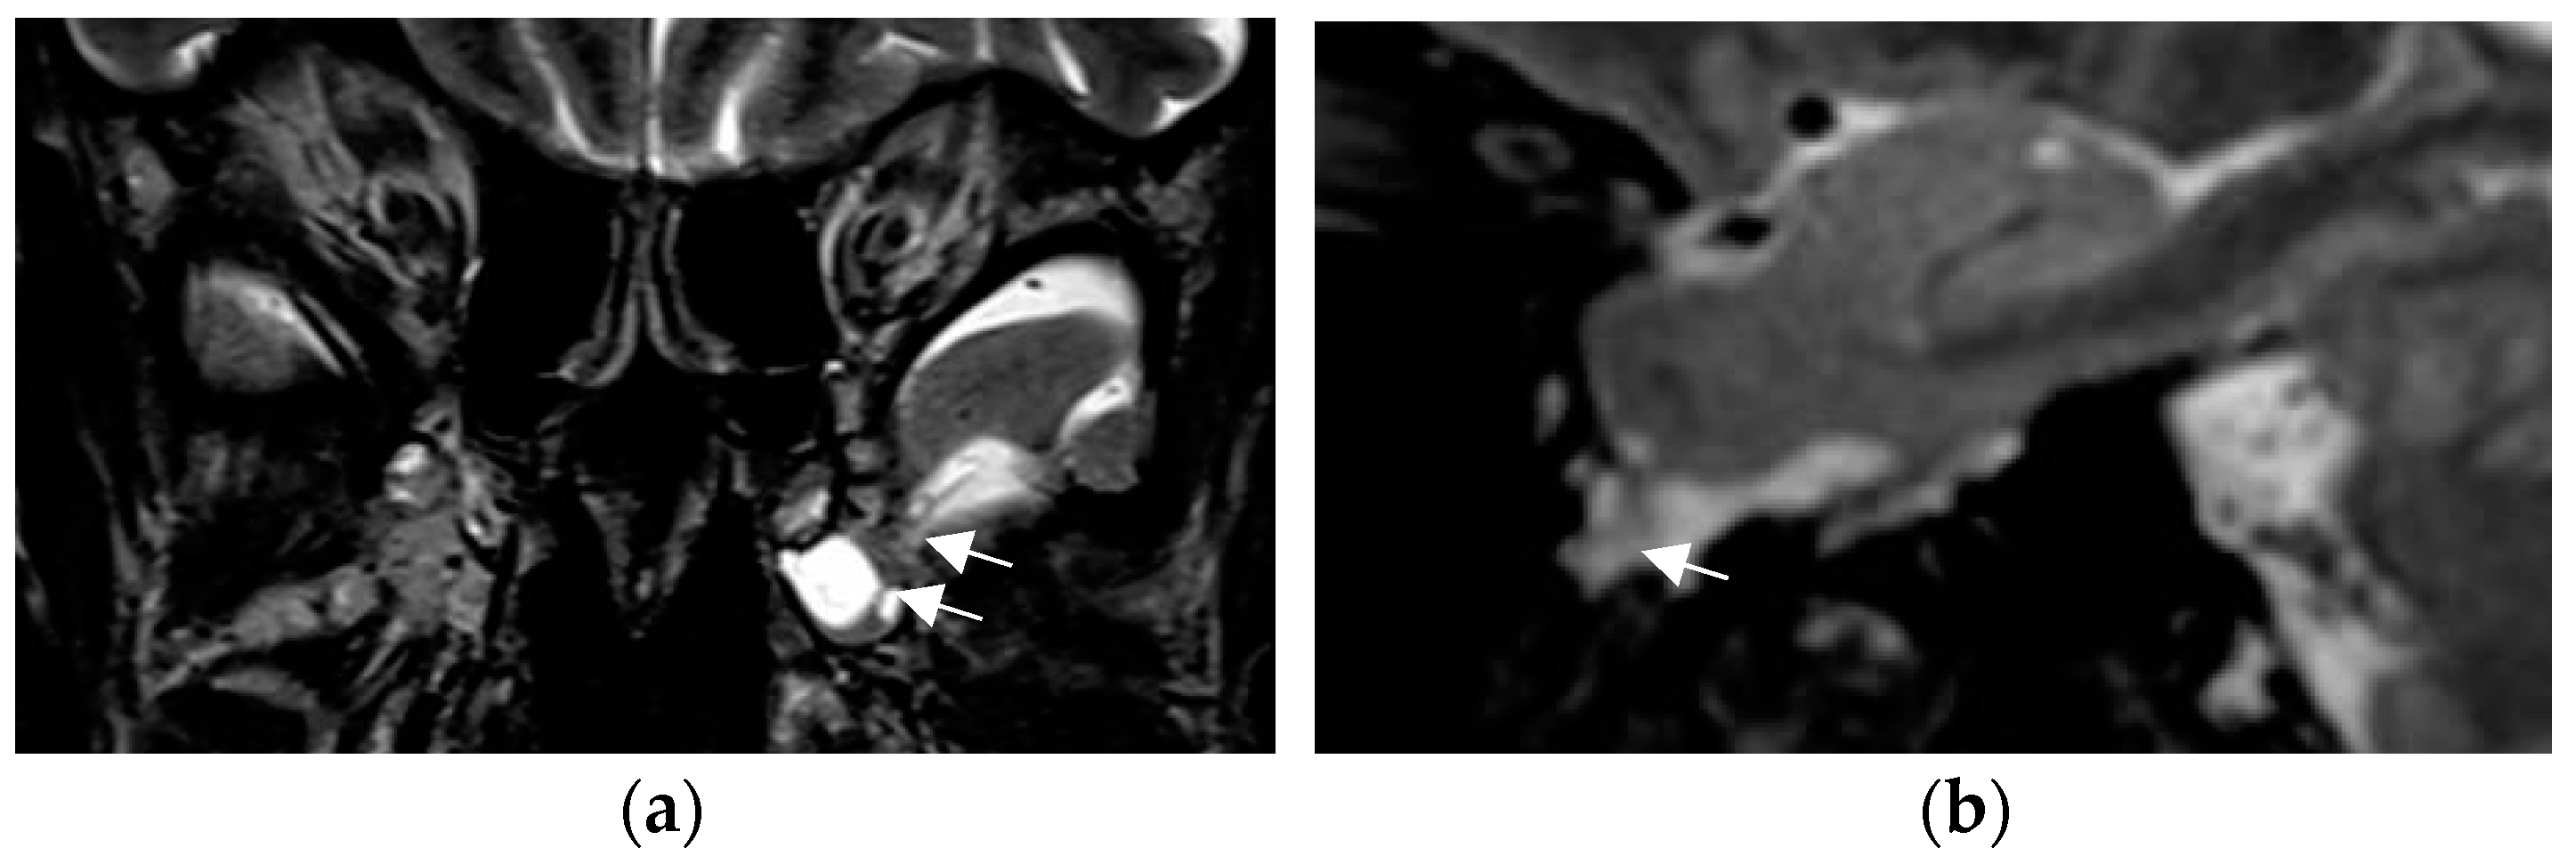

A practical tip is to increase the spatial resolution in a 3T field magnet by lowering slice thickness from 3 mm to 2–1.5 mm for T2 sequences while maintaining signal intensity. This is enabled by application of a head coil with a high number of receive coils—e.g., 64 channels in a 3T field system (Figure 3). Sensitivity for lesion detection is thus increased from 53.1% to 85.9% [72]. The most common pathologies additionally encountered in this study were FCD, nonspecific gliosis, and oligodendrogliosis.

Figure 3.

Mild malformation of cortical development along left central sulcus hardly depicted by slight cortical blurring and subcortical gliotic foci on 1.7 mm coronal T2 w image (arrow in (a)) (a). Improved visualization of the mMCD on sagittal (b) and coronal (c) MP2RAGE sequence (0.9 mm) with slight nodular irregularity of both cortical borders and focal subcortical extension (c).

Progressive substitution of 2D acquisition with 3D acquisition and thus lowering the slice thickness from 2–3 mm slice to 0.9–1 mm (=submillimetric) is a considerable yield-gaining strategy. This not only increases visual conspicuity for small lesions but moreover enables advanced postprocessing of 3D data.